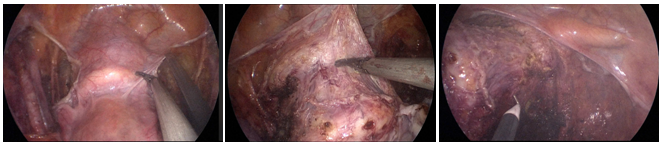

Figure 3 Intraoperative Images: 3A: there was no effusion and no adhesion in the pelvic cavity. Uterus and bilateral adnexa appeared normal.

Initially, the right-side infundibulopelvic ligament in high position was dissected (Figure 6). Next, the right-side anterior and posterior lobes of broad ligament were opened (Figure 7). After which the peritoneum incision was extended to in front of aorta abdominalis, exposing the right-side ureter. The lateral peritoneum was then cut to the bottom of right-hand round ligament of uterus (Figure 8). At this point the pelvic lymph node dissection was begun. The lymph nodes were dissected in the following order; common iliac artery nodes (Figure 9), external iliac nodes (Figure 10), inguinal nodes, obturator nest nodes (Figure 11), internal iliac nodes, and nodes of the main ligament of the uterus. After lymph node dissection the right uterine artery was ligated (Figure 12). The same process was repeated on the left side of the uterus. Peritoneal reflections of the uterus and rectum were separated, and the rectum was separated from the posterior wall and upper segment of vagina (Figure 13).